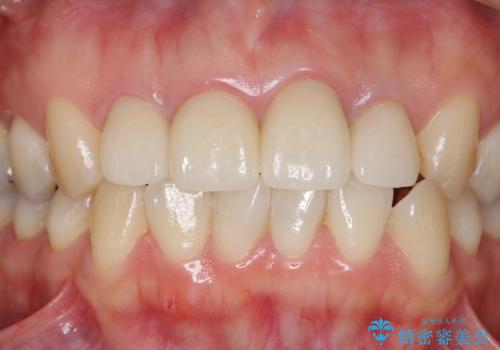

金属のフレームを用いるクラウンは色調が暗くなる傾向にありますが、セラミッククラウンに置き換えたことで自然な明るさ、審美性を取り戻すことができました。

黒っぽい歯ぐきを改善したい メタルフリーセラミック治療

- 44万円(エコノミークラウン×4・ファイバーコア×4・仮歯×4)費用は治療当時の料金となります